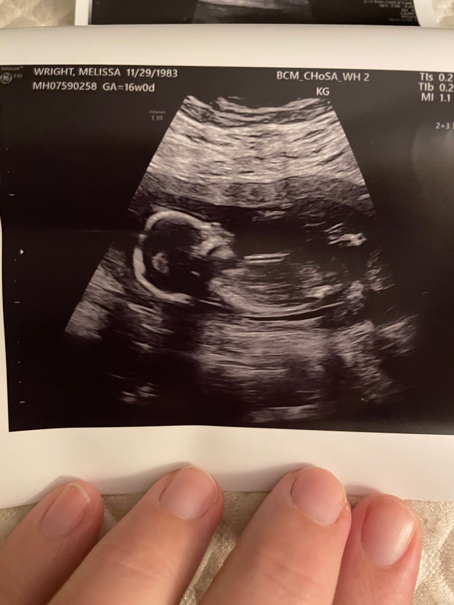

Melissa’s first trimester was smooth, and by the time she reached her 20-week ultrasound appointment, she was feeling more and more confident about the day she would soon welcome their rainbow baby, a little girl, into the world.

Because of her age and previous miscarriage, Melissa had regular appointments with a Maternal Fetal Medicine specialist for extra monitoring. During her 20-week ultrasound, which measures the growth and development of the baby through a comprehensive scan, she noticed that her technician spent extra time examining the heart. Not long after, her Maternal Fetal Medicine specialist sat Melissa and her husband down and explained that there was some concern about the baby’s development.

Melissa Wright Ultrasound